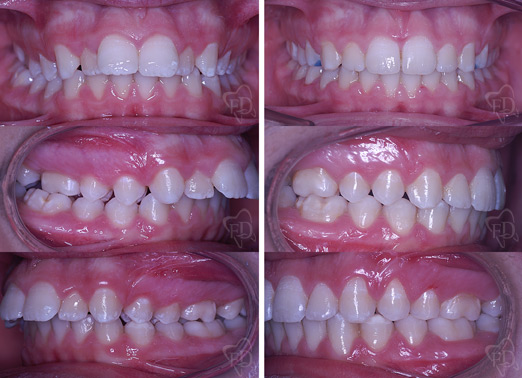

Terapia intercettiva:

prima dopo